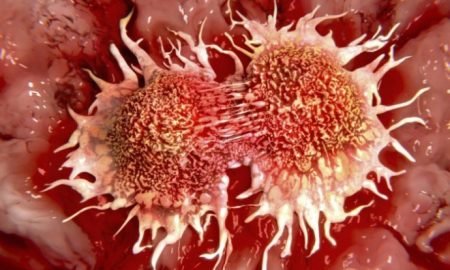

34.0KNaukaVeliko otkriće belgijskih naučnika u borbi protiv raka

BRISEL - Tim profesora Sedrika Blanpena, pri Slobodnom Univerzitetu u Briselu identifikovao je protein koji omogućava ćelijama raka da se odupru hemoterapiji.